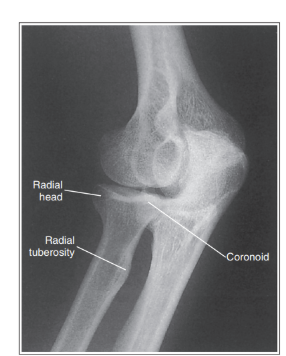

Radius and ulna are not superimposed, but coronoid can be seen

Over-rotation with obliquity of more than 45 degrees